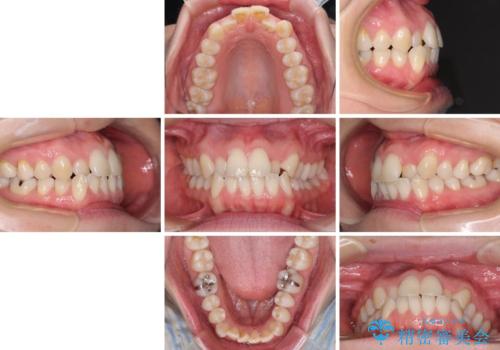

- 受け口傾向でクロスバイトの前歯を治したいとのことで来院された患者様です。

下顎骨が若干左側に変位していたため、右側にアンカースクリューを使用し、積極的に移動させながらインビザラインにて矯正治療を行うこととしました。

インビザラインによる矯正治療は、受け口傾向の治療に非常に適した方法であり、事前にシミュレーションに沿って治療を進めることできます。

今回の治療では骨格的な偏位があったためアンカースクリューを使用し、より確率の高い治療を行うことができました。